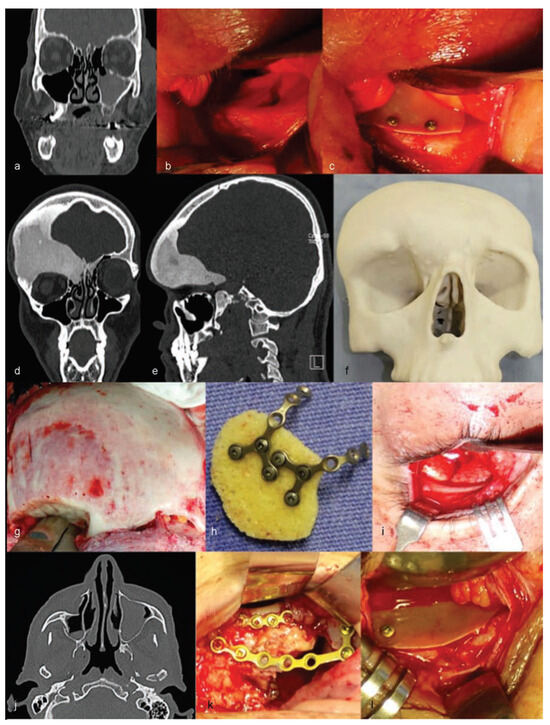

The authors are experienced with the use of castor oil polymer prostheses in several cases of trauma and surgery for camouflage deformities (Figure 1 and Figure 2).

The custom castor oil polymer prosthesis (Poliquil Araraquara Polímeros Químicos, LTDA, Araraquara, Brazil) had the following specifications: dimensions of 125 × 110 × 05 mm; reference no. 3.000.02; registered with the Agência Nacional de Vigilância Sanitária do Brasil (ANVISA; National Agency for Sanitation Oversight of Brazil)—no. 1.03.056.9.0013; lot no. 053.381.001; made and sterilized on November 28, 2012; and with an expiration date of November 2015 (Figure 8).

Following adaptation of the prosthesis to the area of bone loss, nine titanium (Ti) microplates (KLS Martin, Tuttlingen, Germany; System 1.2 mm) were used to ensure the attachment of the plates to the skull (Figure 9). In the next step, a pericranial flap taken from the adjacent area, in which the expander was implanted and fixed with resorbable Vicryl 3–0 suture, was used. This was followed by the installation of a drainage vacuum, and then the edges of the surgical wound were closed using Vicryl 2–0 sutures, and the synthesis of the skin was completed using Stapler SW35 mechanical sutures. The exit for the drainage vacuum was attached to the skin with Nylon 3–0 thread. The covering used was a compression bandage with a crepe dressing.

Figure 9. (a) View of the segment of the prototype reproducing the bone defect in the temporoparietal region. (b) Transoperative view of the bone defect. (c) View of the castor polymer positioned in the prototype, simulating the desired reconstruction. (d) Transoperative view of the castor polymer prosthesis in fixed position.